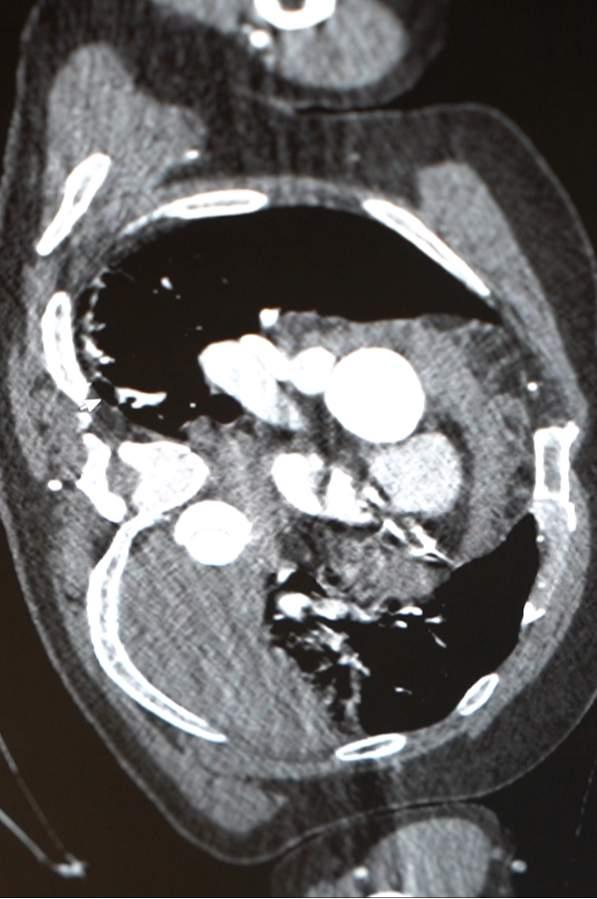

修理师傅弯腰修水管,身体的“主水管”却突然喷血,心脏几乎“空转”!医生提醒:如出现这种症状请立即就医。 近日,陕西西安的修理师傅章先生经历了惊险时刻。当天,章先生正在修理水管,而下一刻他自己的“生命水管”开始疯狂渗血——作为人体血液总管道的胸腹主动脉撕裂,血液正从破口喷涌,左侧胸腔已有1700ml积液,相当于成人全身血量三分之一!他的心脏几乎在“空转”。这是一起极其危急的急症——主动脉撕裂。主动脉是人体中最主要的动脉,负责将血液从心脏输送到全身。一旦主动脉发生撕裂,血液会迅速从血管内喷涌出来,导致大量出血和血容量的快速丧失,危及生命。 关键点分析: 主动脉撕裂的严重性:主动脉撕裂是一种急性、危及生命的疾病,常由高血压、主动脉壁弱点或创伤引起。其症状包括突发剧烈背部或胸部疼痛,疼痛可能呈撕裂样或刀割样。 症状表现: 突然剧烈的胸背痛 出血(如新闻中提到的“喷血”) 休克表现(血压下降、面色苍白、出汗、意识模糊) 心跳加快,甚至心脏“空转”——指心脏因缺血或休克而几乎无法正常泵血。 紧急处理: 立即拨打急救电话 维持呼吸道通畅,避免移动患者 控制出血(如止血带等,需专业操作) 迅速送医,进行手术修复 预防与提醒: 高血压患者应定期监测血压,遵医嘱用药 养成健康生活习惯,避免剧烈运动或创伤 任何突发胸背剧痛都应引起重视,及时就医 总结: 主动脉撕裂是一种极其危险的急症,患者若出现类似剧烈胸背痛、突然出血、意识模糊等症状,应立即就医,争取黄金时间进行救治。公众也应提高认识,重视血压管理和身体信号的变化,以预防此类事件的发生。大动脉爆裂